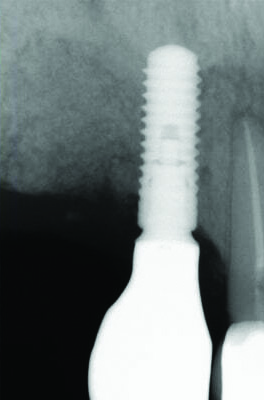

Fig 3 and Fig 4. Case 2: Initial clinical presentation showing implant No. 6 with RPI, having been impacted by fractured tooth No. 5 (Fig 3); radiograph showing fractured tooth No. 5 with periapical lesion extending to the distal aspect of implant No. 6 (Fig 4).

Fig 4. Case 2: Initial clinical presentation showing implant No. 6 with RPI, having been impacted by fractured tooth No. 5 (Fig 3); radiograph showing fractured tooth No. 5 with periapical lesion extending to the distal aspect of implant No. 6 (Fig 4).

Patient 2: A 63-year-old healthy male patient presented with implant No. 6 exhibiting RPI, having been affected by previously endodontically treated and fractured tooth No. 5 (Figure 3 and Figure 4). The implant had probing depths ranging from 4 mm to 10 mm (Table 1) with the most severe bone loss at the distal aspect of implant No. 6 (Figure 3 and Figure 4).